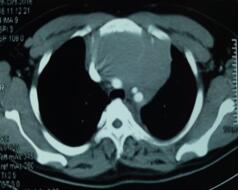

當(dāng)看到病人的CT等外院各項(xiàng)檢查時(shí),我頭皮發(fā)麻,心頭發(fā)怵:巨大的腫塊占據(jù)著整個(gè)縱隔,壓迫心臟,與血管關(guān)系密切,初步考慮侵襲性胸腺瘤、胸腺癌或淋巴瘤等,合并腎功能不全,無(wú)法完整切除,手術(shù)風(fēng)險(xiǎn)大,手術(shù)并不能提高病人長(zhǎng)期生存率,換言之,小伙子等待的是生命的立即終結(jié)。

當(dāng)看到病人癥狀緩解,復(fù)查胸部CT幾近完美,我們那種自豪感油然而生。偶爾去治愈,常常去幫助,總是去安慰,我們深知,小伙子的人生之路并不長(zhǎng),只能深深祈禱他在我們的治療下能走得更遠(yuǎn)一些,能把剩下的日子走的更充實(shí)一些。而我們?cè)谀軌驇椭说臅r(shí)候,別一味地去安慰,永不言棄,是我們這一群胸外人堅(jiān)貞的信念。